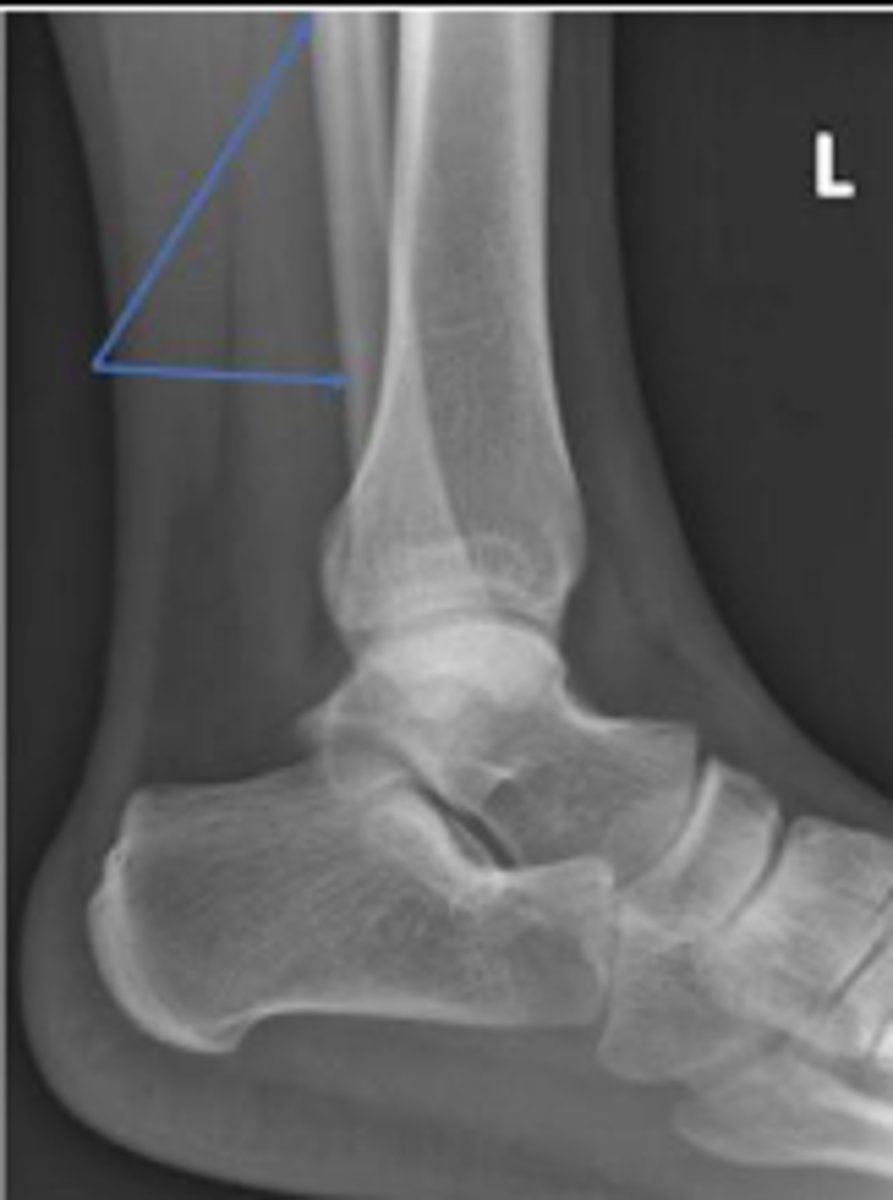

Left AP ankle

What is the name of the radiographic view?

Axial relationship of the ankle

What is the overarching name of the assessment?

Tibial angle & fibular angle

What are the 2 components of the assessment?

Tibial angle

What is the name of the assessment?

Yes

Is the assessment within normal limits?

Fibular angle